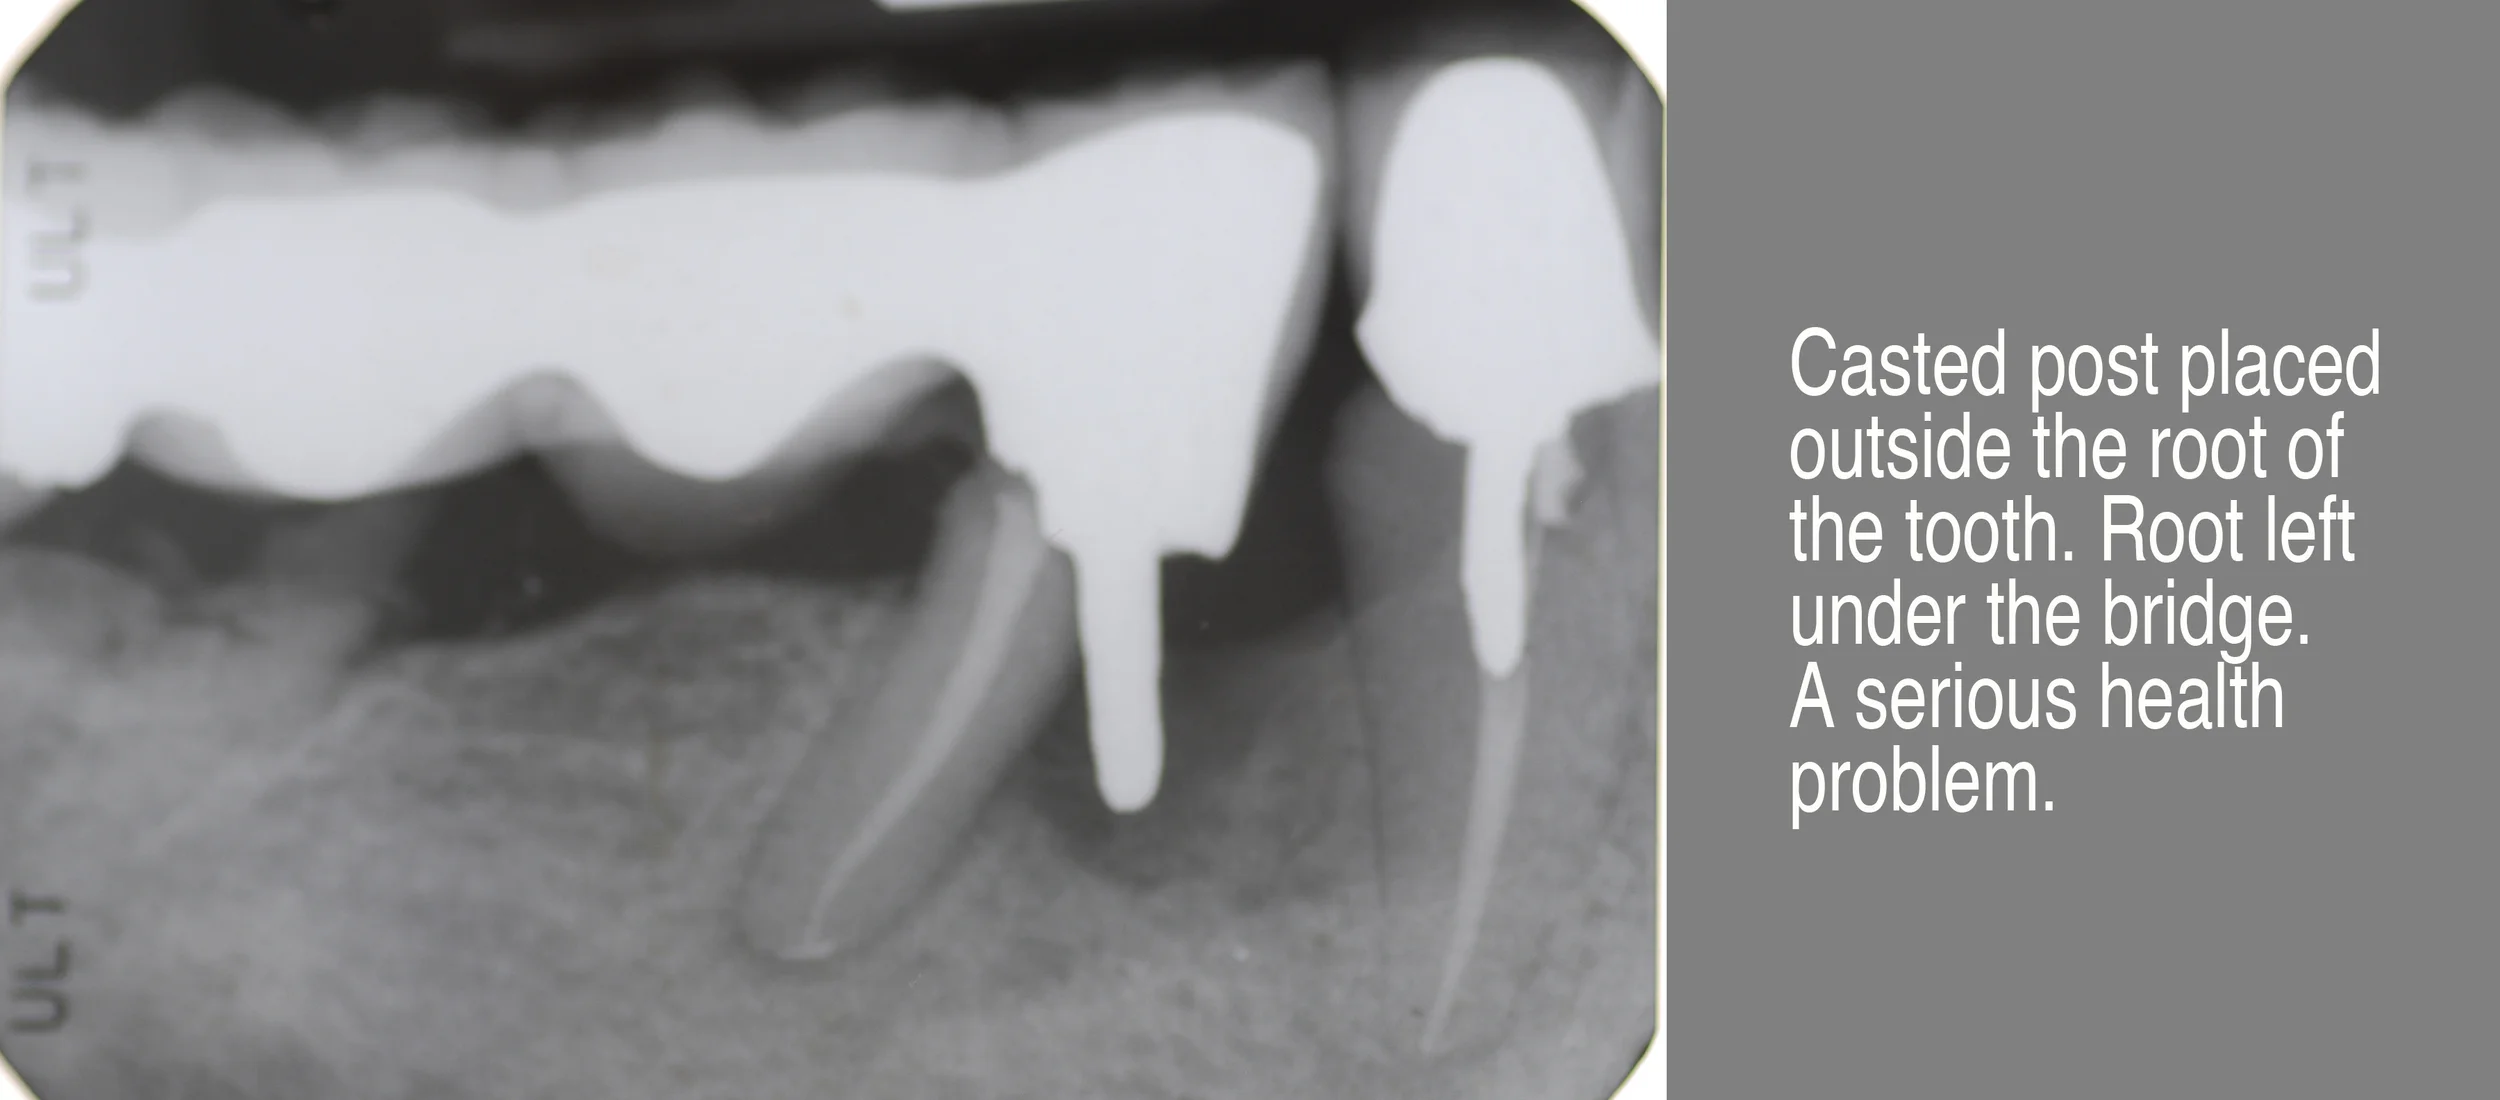

• Malpractice Repair